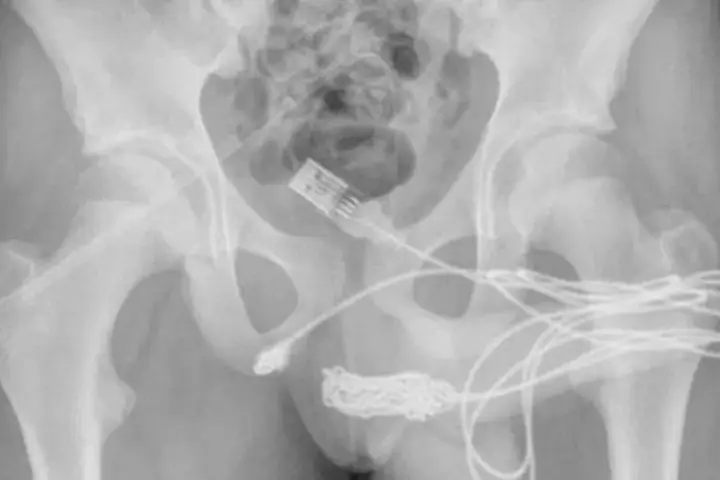

Um adolescente de 15 anos teve que ser submetido à uma cirurgia de emergência após ficar com um cabo USB preso dentro da uretra após, segundo ele, utilizar o fio para medir o interior do próprio pênis.

Após alguns Raio-X os médicos constataram que o fio havia dado um nó dentro do corpo do rapaz e só poderia ser removido cirurgicamente, através de uma incisão entre o pênis e o ânus do adolescente.

Segundo relatado ao Daily Mail, os médicos puxaram a extremidade do cabo, cortando-o do resto do fio antes de remover os pedaços restantes.